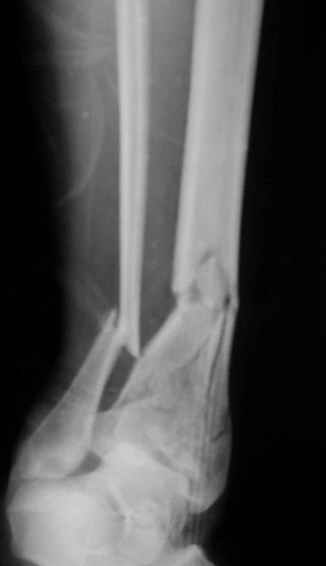

Открытый оскольчатый перелом н/3 голени.

Здравствуйте, коллеги! 16/10/06 г. В отделение поступила больная с производственной травмой - Открытый оскольчатый перелом метафиза и метадиафиза обеих костей правой голени со смещением отлоков.

Здравствуйте коллеги! В данной ситуации я полностью согласен с мнением Александра Николаевича! Практически любой внутрисуставной(тем более приведенный на снимках) перелом требует открытой репозиции.Судя по приведенным рентгенограммам, в области дистального тибио-фибулярного сочленения имеется "минус" ткань на tibia, которая может потребовать костной пластики.Метод фиксации любой,главное ранние движения в суставе. С уважением Руслан Ш.

К слову, тема этого обсуждения обозначена неточно, тут перелом дистального суставного конца типа 43-C, а не "открытый оскольчатый перелом н/3 голени", т.е. диафизарный, 42-.

Действительно, речь идет о сложном внутрисуставном, да еще и открытом переломе 43С.3.

1. Представленные рентгенограммы во-превых плохого качества (ну да ерунда), а во-вторых (самое главное) - в нестандартных проекциях. Невозможно оценить количество и положение фрагментов суставной поврехности. Собственно это делает обсуждение бессмысленным. Мы обсуждаем не конкретный случай, а вообще...